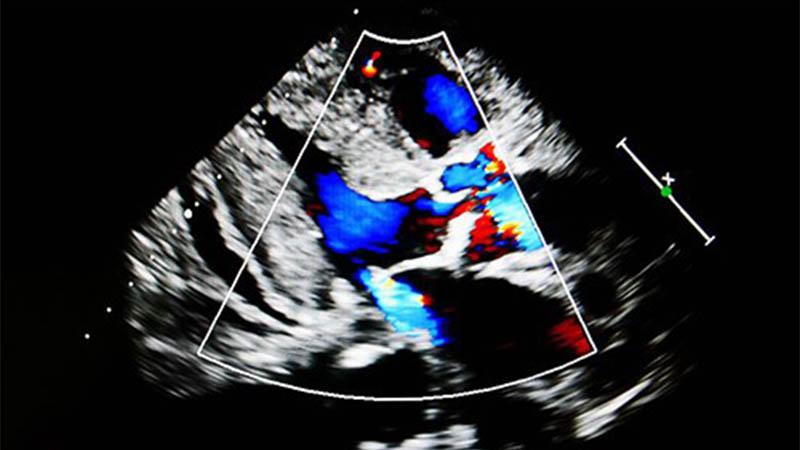

Ultrasound flow color mode show jet from aortic and mitral valve regurgitation

Of PRIMARY Importance: Surgical or Percutaneous Repair for Mitral Regurgitation?

In recent years, surgical replacement and repair and transcatheter edge-to-edge repair (TEER) have become comparable options to treat primary, degenerative mitral regurgitation in high risk patients. A NewYork-Presbyterian/Columbia interventional cardiologist is one of two study directors leading the PRIMARY Trial, a prospective, open-label, randomized trial comparing surgical repair to mitral valve TEER with a commercially approved edge-to-edge mitral repair device. Through the PRIMARY trial, researchers are seeking to develop well-founded criteria that will guide advanced decision-making about which patients are best suited for a transcatheter approach and those who would do better with surgery.